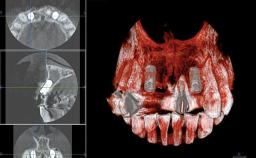

This 20-year-old woman was referred to our department in July 2006. Four months earlier, she had experienced dental trauma to the anterior maxilla when traveling in South America. The emergency treatment included emergency root canal treatment of teeth 12 and 11. Tooth 21 was also subjected to endodontic treatment later. At the initial examination, the patient was not in pain but reported increased mobility of tooth 12. The clinical examination revealed a high smile line, medium thickness of the soft tissue, and rectangular tooth forms. Discoloration of tooth 12 was evident. The periapical radiograph provided by the referring dentist indicated a fracture line at both teeth 12 and 11. A cone-beam computed tomography (CBCT) scan confirmed these fractures. No pathology was found to be associated with tooth 21.

Bone Augmentation Horizontal|Simultaneous

Augmentation Materials Autogenous chips|Xenogenous|Membrane

Bone Volume Deficient horizontally, allowing simultaneous augumentation